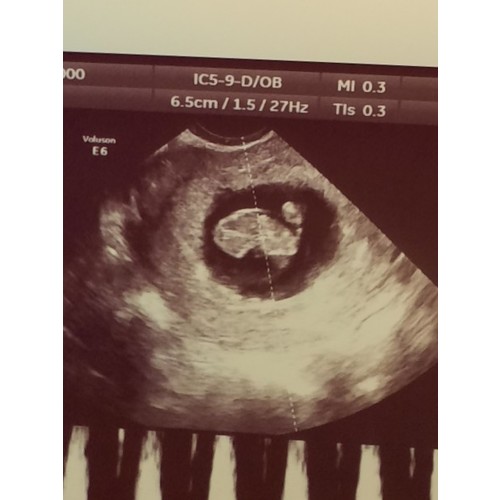

Ligt een beetje aan de verloskundige waar je zit. Bij de verloskundige waar ik bij zit is dit een medische echo. De vitaliteits echo. Waar ze kijken of er een gezonde zwangerschap is en of het een een of een meerling is. Dit doen ze vaak tussen de 7 en 9 weken.

Helaas moeilijk tezien gisteren echo gehad ban 8+5 maar mijn baarmoeder ligt nog wat verder naar achter dus niet zn hele helderen echo maar hartje klopt en alles was goed 😍😍